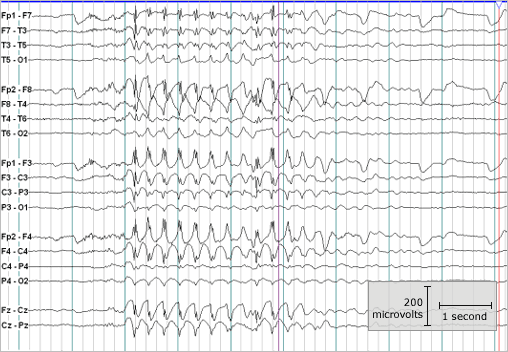

Fast forward 12 years, he had an EEG done with a caring staff revealing seizure activity all day, all night and in every area of his brain. He has probably been experiencing it for a long time as he cannot sleep and his symptoms have not been as responsive to other treatments as we had hoped. My heart aches that a proper 24 hour EEG was never suggested by his doctors. I am leaving those feelings behind because I am hopeful that during this 15th year of life I will hear his voice. I am hopeful that he will finally be able to sleep, show me his strengths and his true potential. Since his diagnosis, I have continued to look for answers for my beautiful son. I share our story to inspire others into seeking treatment and to demonstrate that hope is ALIVE and well at my house!